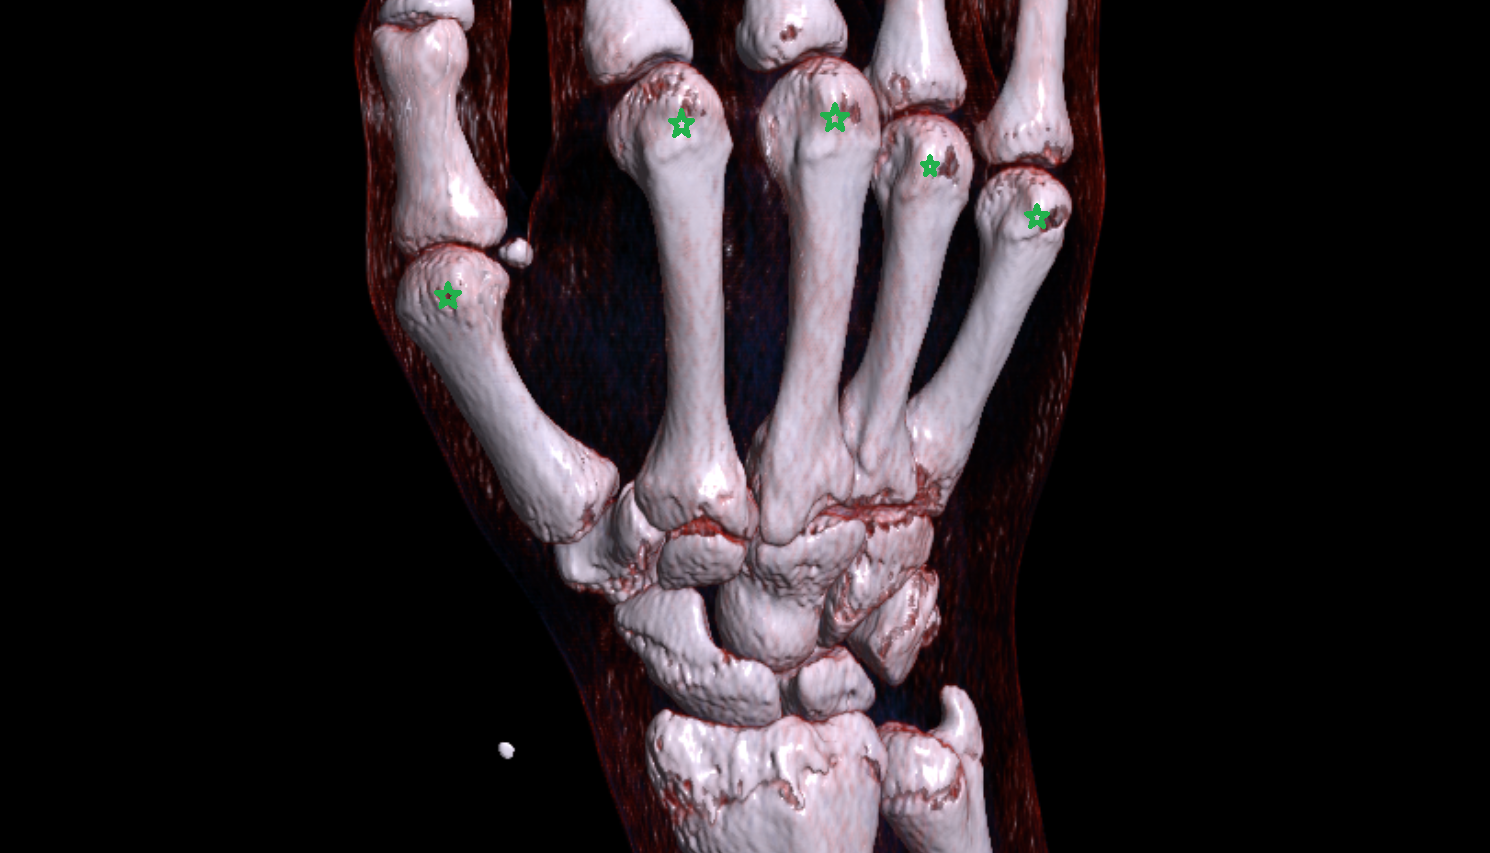

- Cubital tunnel